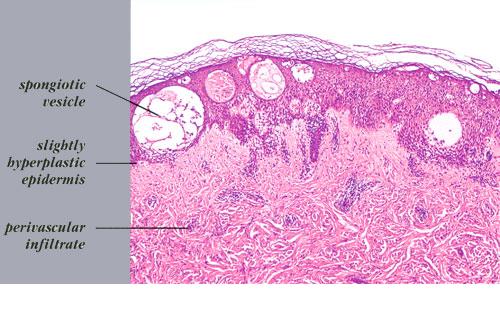

Acute contact dermatitis = التهاب ا لجلدالحاد بالتماس